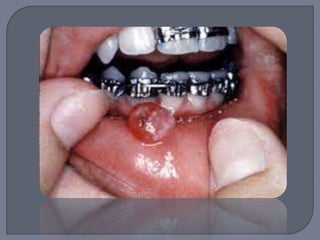

Lesión elevada localizada de tejido de

granulación

Masa exofítica a veces lobulada y ulcerada

Por lo general pedículada

Color rojo o rojo púrpura

Tendencia a sangrado

Diámetro de milímetros a centímetros

Es necesaria la extirpación quirúrgica de toda

la lesión

Si involucra dientes debe hacerse raspado y

alisado

Si la lesión recidiva entonces es probable que

haya que extraer el diente involucrado